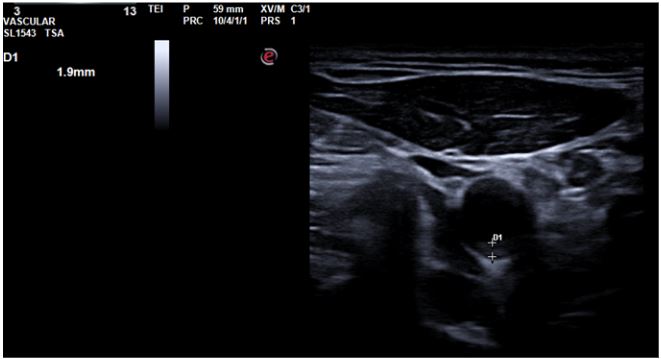

De esta forma, comenzamos a utilizar la ecografía no solo como herramienta diagnóstica, sino también como instrumento de concienciación visual. Así, mostramos en directo al paciente sus placas de ateroma en carótidas o femorales, o la hiperecogenicidad hepática fruto de su esteatosis. Al ver su daño, muchos cambian de actitud. Frases como «¿esto está dentro de mí, doctora?» se repiten, y suelen ir seguidas de decisiones reales. Ese momento es mágico. La negación se rompe. La conciencia se enciende. El cambio empieza. Tras ver sus imágenes, pacientes que no tomaban tratamiento empezaron a hacerlo. Fumadores empedernidos pidieron ayuda. Personas que decían «ya adelgazaré» empezaron a perder peso. Todo, porque lo vieron.